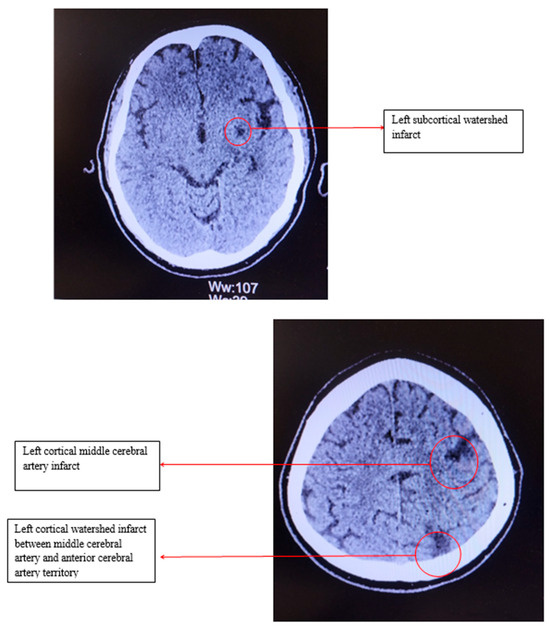

Electrocardiography revealed sinus bradycardia, with a heart rate of 46 bpm and no ST/T changes. Cranial computed tomography showed several chronic infarction areas in the left frontal, left parietal, and in the left internal capsule (Figure 1).

Figure 1.

Computed tomography of the head.